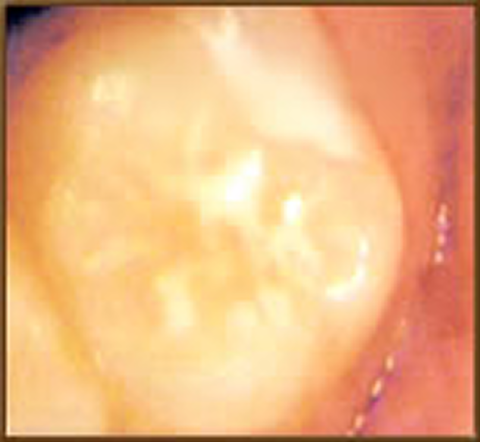

シーラント

歯みがきの難しい「奥歯のみぞ」は、食べカスやばい菌がたまりやすく、ムシ歯に大変なりやすいと言われています。 「シーラント」はこの「奥歯のみぞ」を埋めてムシ歯菌を防ぐ材料です。

「シーラント」には歯を強くして、ムシ歯菌から守る「フッ素」も入っています。

とっても簡単な処置でムシ歯になりにくい歯に!

シーラントでムシ歯菌から歯を守りましょう。